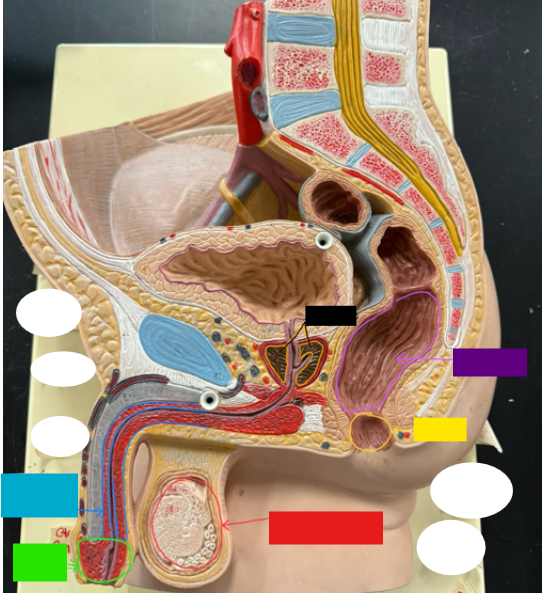

What is the name of the red box?

Ureter

What is the name of the red box?

Vas deferens

What is the name of the yellow box?

Seminal vesicle

What is the name of the blue box?

Prostate

What is the name of the light green box?

Epididymis

What is the name of the light blue box?

Prepuce

What is the name of the blue box?

Corpus spongiosum

What is the name of the light green box?

Glans penis

What is the name of the red box?

Seminiferous tubules

What is the name of the black box? X2

Prostate

What is the name of the purple box?

Rectum

What is the name of the yellow box?

Anus

What is the name of the red box?

Scrotum

What is the name of the orange box?

Corpus cavernosum

What is the name of the light blue box?

Spongy urethra

What is the name of the red box?

Prostatic urethra

What is the name of the pink box?

Ejaculatory duct

What is the name of the yellow box?

Membranous urethra

What is the name of the brown box?

Testis